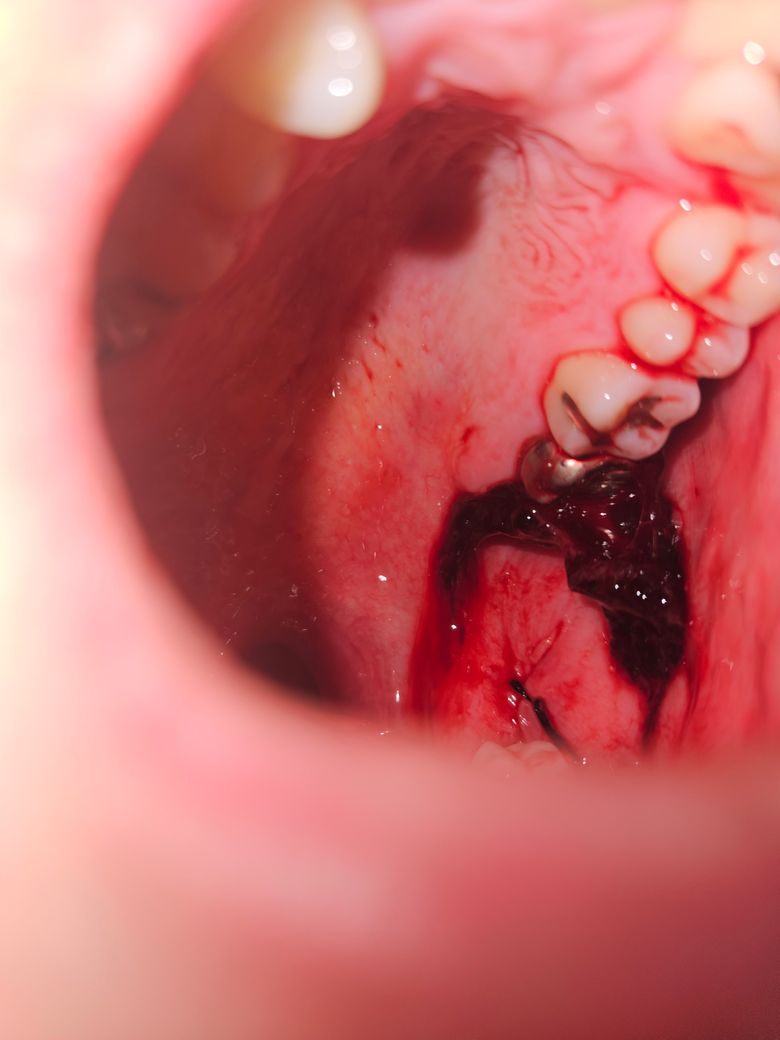

사랑니 발치 다음날 자고 일어나니 혈병이 커졌습니다.

어제 위 아래 사랑니 발치했습니다.

아래는 매복이었고 위는 일반 발치했습니다.

자기전에는 이렇게 큰 혈병이 없었던것 같은데 자고 일어나니 아래의 사진처럼 되었습니다.

해당사진으로 판단하실수있을지 모르지만 최선이었습니다. 혼자서 찍으려니 쉽지 않네요...

내원한 치과가 일요일은 진료하지 않아 글을 올리게 되었습니다. 이대로 둬도 괜찮은 것인지 일요일 진료를 하는 다른 치과라도 방문해야하는 것인지 궁금합니다.

+아침식사를하고 양치하다가 떼졌습니다... 이후 피가 조금씩 나오는거 같습니다. 이것도 문제가 될까요?